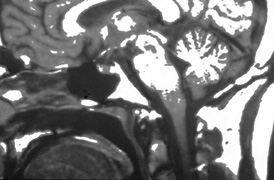

Aicardi's syndrome consists of agenesis of the corpus callosum, chorioretinal lacunae (Fig. 13), and infantile spasms with seizures. The condition is limited to females and, with one exception, is lethal in males. Additional ocular features may include microphthalmia, optic nerve colobomas, peripapillary glial tissue, and variants of persistent fetal vasculature.63,64 Affected children rarely achieve developmental milestones beyond 12 months, and vision is decreased because of combined anterior and posterior visual pathway disease.65

Fig. 13. Fundus of a 3-year-old girl with Aicardi's syndrome. Note dysplastic optic discs surrounded by hypopigmented retinal lacunae. (Courtesy of John T. Flynn, MD)